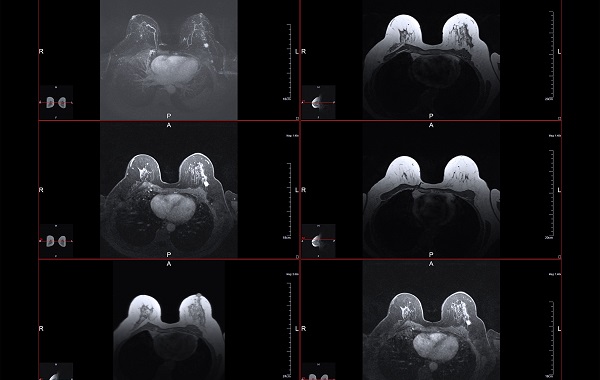

Chẩn đoán hình ảnh tuyến vú bằng MRI

Chụp cộng hưởng từ (MRI) tuyến vú là phương pháp sử dụng nam châm và sóng vô tuyến để tạo ra hình ảnh cắt ngang chi tiết bên trong vú.

MRI không sử dụng tia X vì vậy sẽ không tiếp xúc với bức xạ trong quá trình chụp. Khi chụp MRI vú, có thể tiêm thuốc tương phản từ vào đường truyền tĩnh mạch trước khi chụp để làm cho khu vực bất thường trong vú rõ ràng hơn.